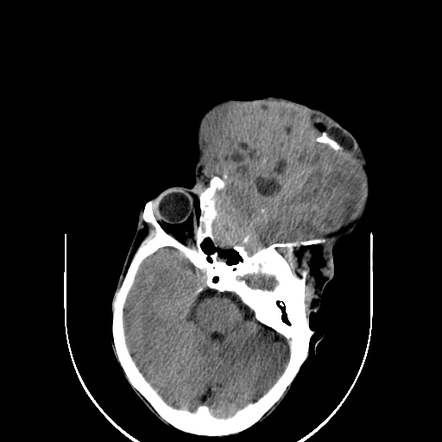

Neurosurgeon India: Orbital Rhabdomyosarcoma

neurosurgeon-india.blogspot.com

neurosurgeon-india.blogspot.com

rhabdomyosarcoma ct scan neurosurgeon india op pre

Computed Tomography And Magnetic Resonance Imaging Observations Of

www.spandidos-publications.com

www.spandidos-publications.com

rhabdomyosarcoma neck head embryonal axial tomography computed imaging magnetic observations resonance ol figure